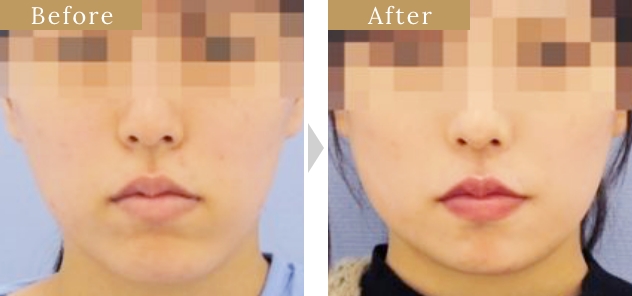

各部位の施術・症例紹介

症例

症例

症例